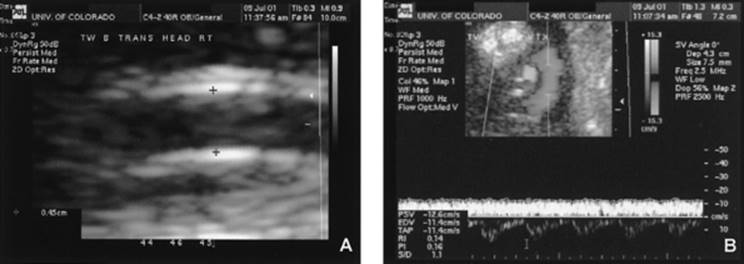

QUANTIFICATION OF FLOW

Until recent advancements in high-resolution digital imaging with simultaneous imaging and Doppler methodologies, the reproducibility and clinical feasibility of flow quantification have been limited. Studies show that umbilical venous flow can be measured accurately (inter- and intra-observer variability <7%) and in a timely fashion (<5 min). These flow measurements have been validated by invasive physiologic preparations in fetal lambs. Ultrasound images and formula for calculation of umbilical venous flow is shown in Figure 12.9. In a longitudinal study, not only was volume flow found to be reduced in the IUGR fetus compared to controls, but the variable responsible for this reduction was a low velocity of blood flow and not the umbilical vein diameter. Interestingly, the low umbilical flow in IUGR fetuses was identified very early in the course of IUGR before Doppler changes in other vessels became apparent. Quantitative flow measurements can even be obtained in very small vessels such as the ductus venous. Quantitative flow measurements are a potentially new-tool approach for the assessment of the growth-restricted fetus since quantification of placental flow to the fetus and its redistribution to the liver and heart is now possible.

FIG. 12.9. The formula for measurement of umbilical venous flow is shown. A: On ultrasound, how to obtain umbilical vein diameter (note that the calipers are placed just inside the specular reflections). B: On ultrasound, how color is used to ensure an angle of insonation at nearly 0 degrees and how Doppler velocimetry is used to obtain a steady umbilical vein waveform velocity. See color figure 12.9.